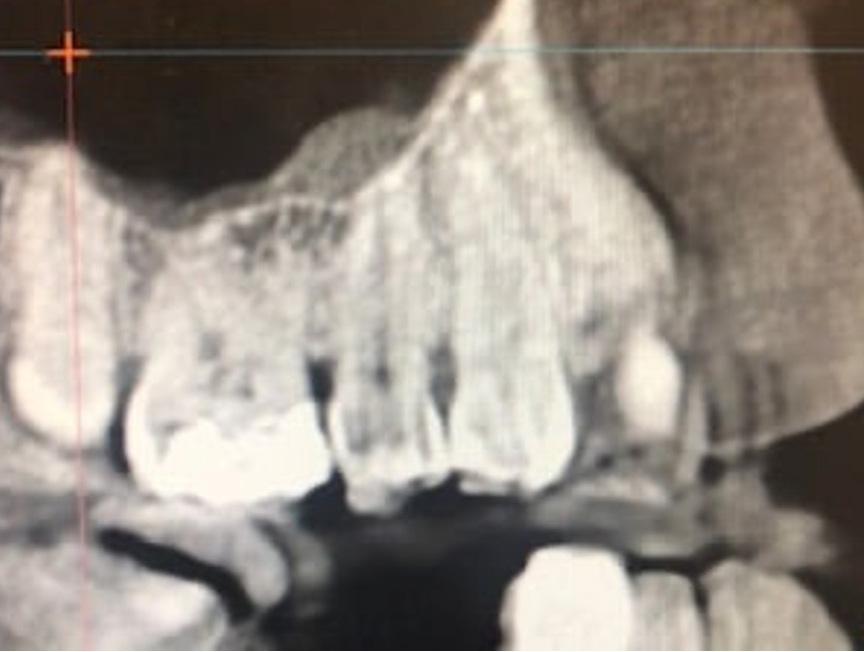

Of course, raising the bar is nothing new to PDS team members. We were the first large dental service organization to move to digital radiography and intra-oral photos, providing faster and better images. Investing in electronic dental records was a natural evolution. Further focusing on the patient brought us to same-day restorations, where we continue to lead the industry with CEREC®. Following in the footsteps of these great advances, we embark this year on a broad rollout of Cone Beam Computed Tomography (CBCT) and the near-complete transition to the Epic ® electronic health record (EHR) system.

CBCT provides oral healthcare professionals with three-dimensional (3D) images that

are a major improvement from traditional X-rays, revealing to clinicians so much more information about their patient’s condition. 3D technology will become the standard of care for all dentists, but once again we are ahead of the curve. Additionally, more than 120 supported offices have already transitioned to Epic, making us the largest single DSO on the platform with a fully integrated EHR system.

30 CLINICAL ENGAGEMENT: PDS-SUPPORTED OFFICES BEGIN DEPLOYING 3D X-RAY TECHNOLOGY

Examine how CBCT is elevating patient care and increasing our understanding of The Mouth-Body Connection

Over the past year, many teams have experienced the integration of Epic and Cone Beam Computed Tomography (CBCT). Looking into the future, the combination of proven technology and understanding the science of The Mouth-Body Connection ® will set us up to deliver unparalleled dental care.

• The use of CBCT will allow us to diagnose conditions that are not visible on 2D radiographs. It will be much easier to evaluate bone levels and detect endo lesions.